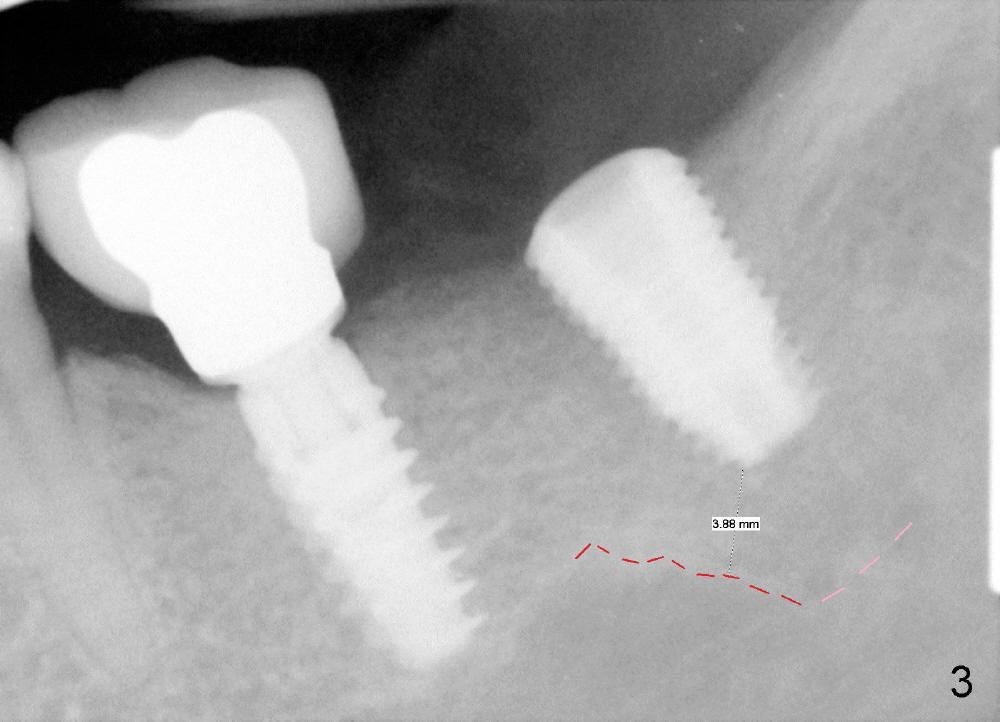

CBCT analysis reveals that there is an abnormal segment of the inferior alveolar nerve (IAN), slightly mesial to the site of #18. Intraop positional PA (Fig.1) shows that it is predictably safe to place 6.3x8 mm implant with the apical diameter (4.3 mm < 2.46 mmx2). Red dashed line indicates the abnormal segment of the IAN (pink line: normal segment). There is also some distance to IAN when 6x11 mm tap is inserted at the depth of 8 mm (Fig.2). Finally a 6.3x10 mm extra wide implant (Brushite) is placed with 3.88 mm from IAN (Fig.3).